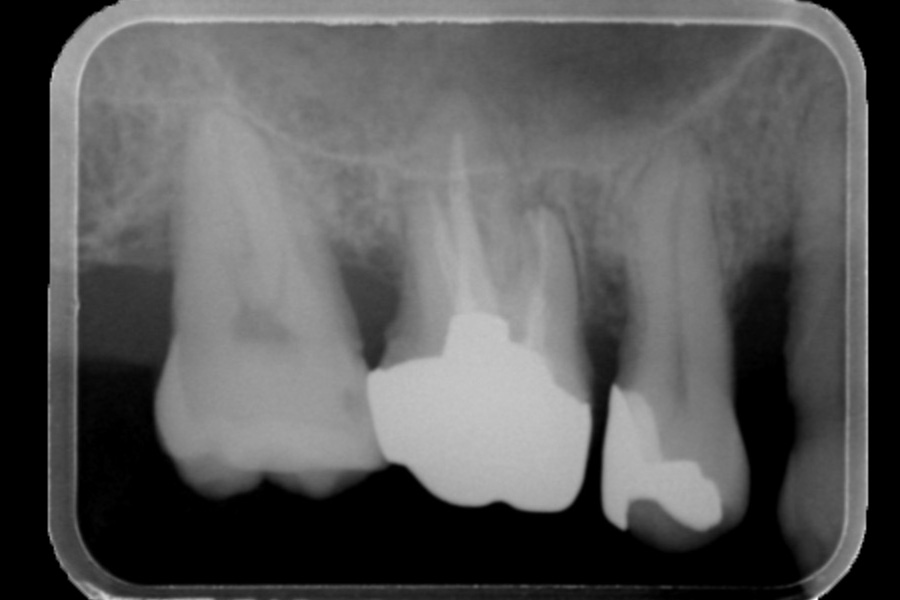

右下奥歯の歯ぐきから出血する

【歯周組織再生療法】

- 担当医

- 清水 宏康先生

- 主訴

- 右下奥歯の歯ぐきから出血する

- 期間

- 再生療法から再評価まで6か月

- 費用

- ¥220,000(税込)

- 治療内容

- 右下4遠心に垂直性骨吸収が認められたためエムドゲインと骨補填材を用いて歯周組織再生療法を行った

- 治療に伴うリスク

- 歯肉退縮、知覚過敏